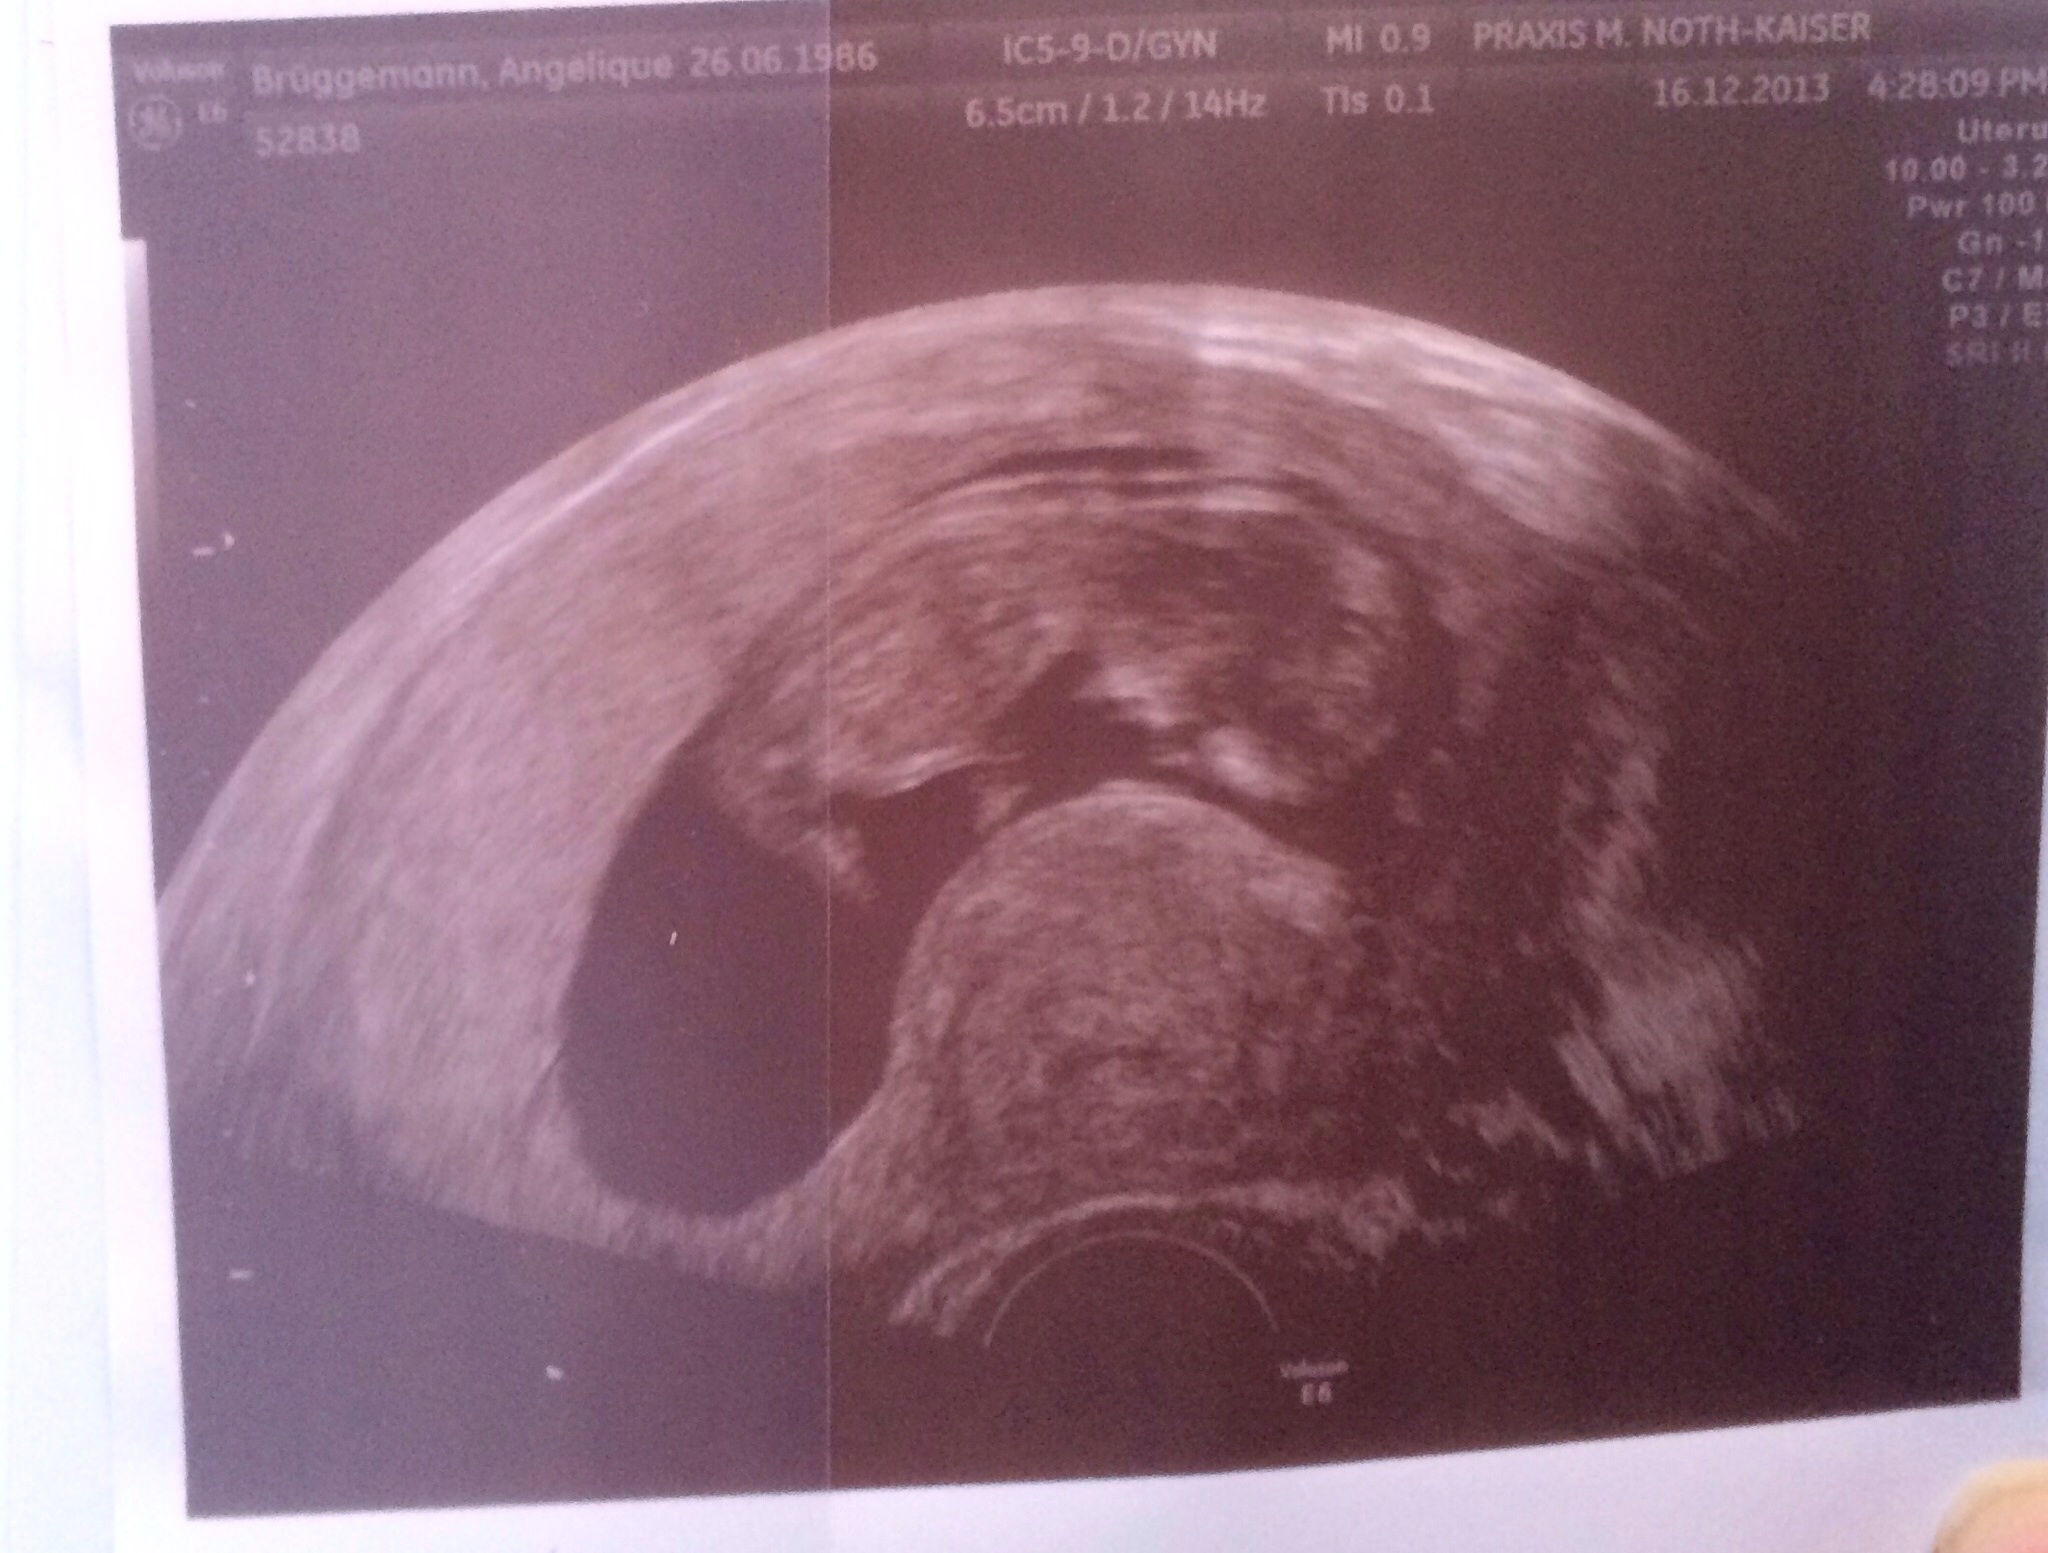

Ich bin in der 13 Schwangerschaftswoche

Baby (ente) 12ssw